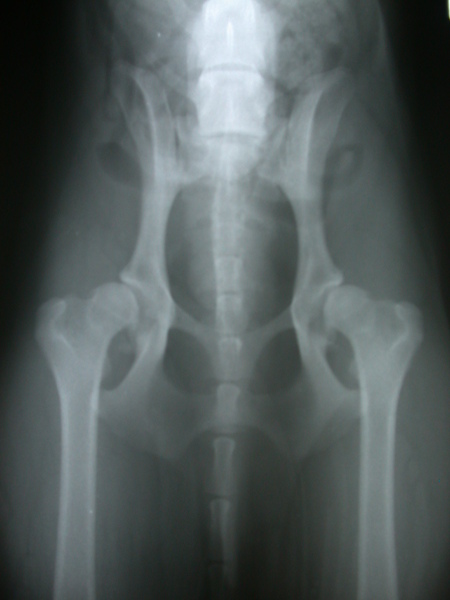

全部選項都是中度和嚴重,只有右腳一個選項是輕微 (茶)

關節重塑形→指的是跟原本的關節長的不一樣了,AMO的關節長了一堆骨贅

Norgberg Angle→醫生忘了幫AMO填上去 ,AMO右腳 83 左腳 85,大於105才算正常

股骨頭包覆率→50%以上較好

王醫師整體評估:AMO兩隻腳都有CHD問題,不過步行OK,沒有一拐一拐的,

我們建議先採用保守的照護方法。若結果無法令人滿意,

再評估要不要換人工關節。

謝醫師說AMO因為關節都變形了,要完全改善只能做髖關節置換手術

以下是AMO的X光片

兩種都各拍了三張